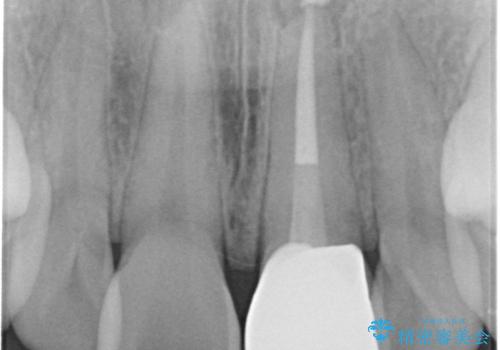

- 前歯の変色を主訴に来院された患者様です。

より審美的な修復を行いたいとのことであったため、ジルコニアクラウンでの修復を行います。

- 左上1 : 仮歯 / 11,000円、ジルコニアクラウン(スペシャル) / 154,000円 合計165,000円(税込)費用は治療当時の料金となります